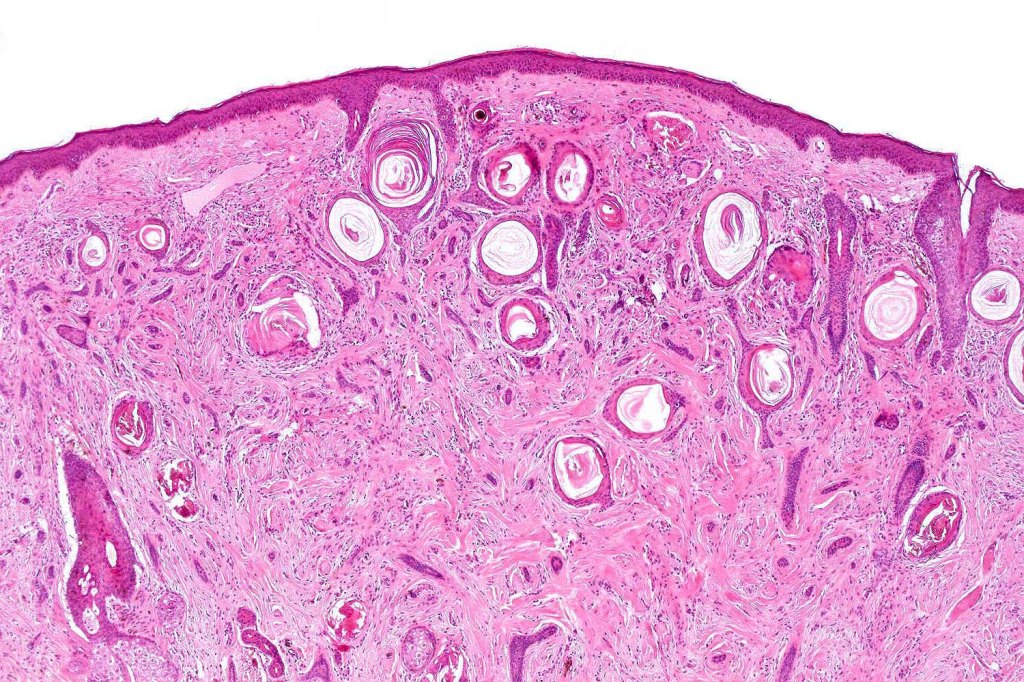

Histology

Histological features

- Keratocysts with epidermoid keratinization

- Pilar keratinization is also sometimes present in the deeper reaches

- Dense fibrous stroma